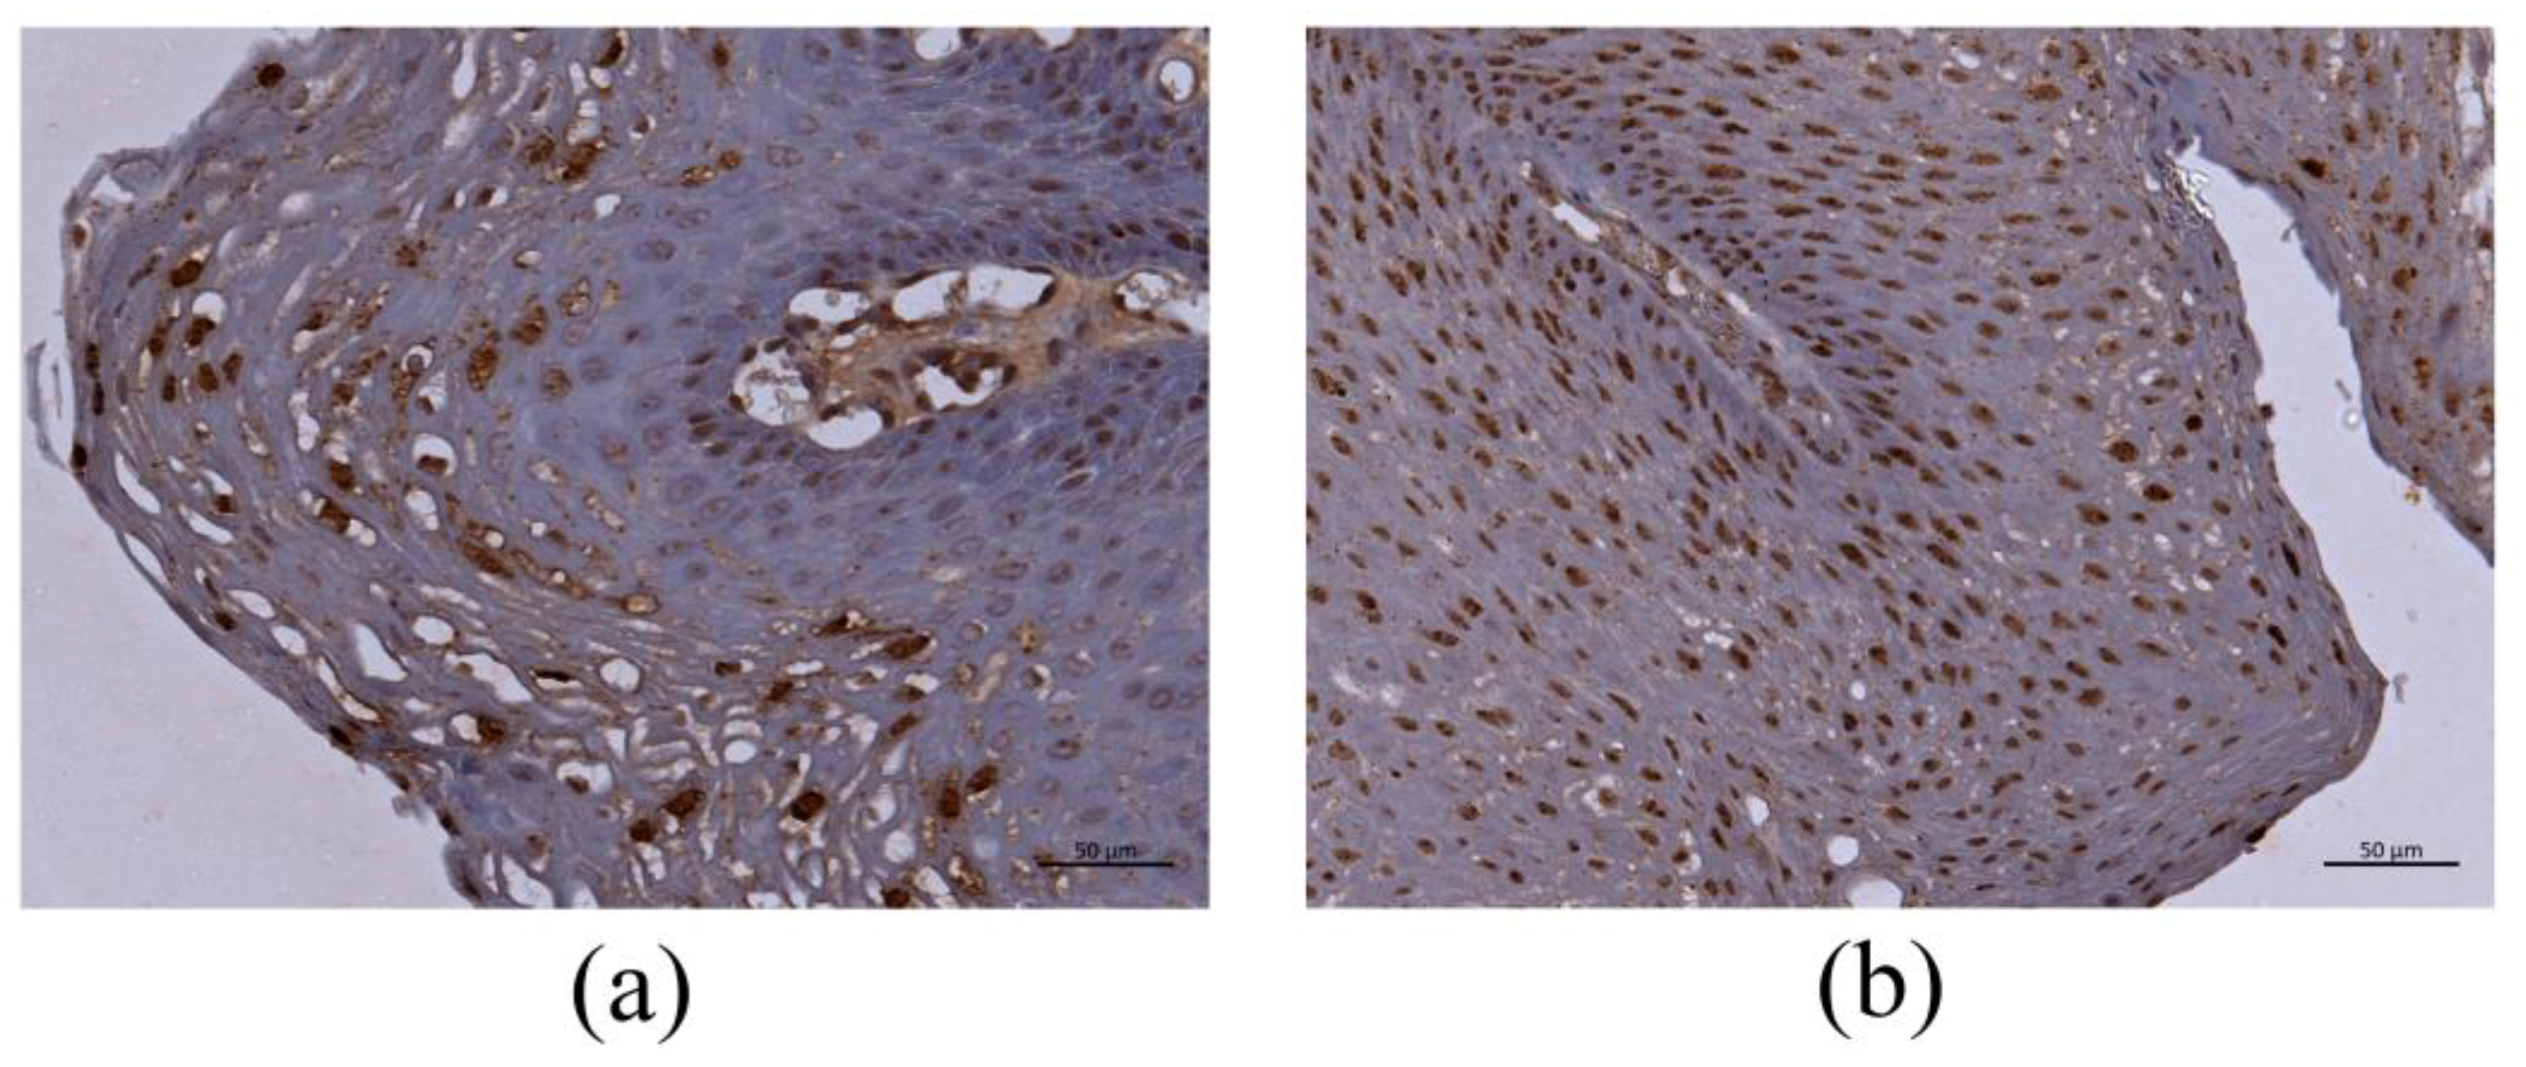

The results of HPV DNA-ISH are shown in Table 3. HPV DNA-ISH generated positive signals in the nucleus and cytoplasm of the infected cells, although the intracellular distribution of the positive reaction pattern was different among the cases. Although the positive signals were distributed throughout LP (Figure 2a,b), there were more prominent reactions in the middle and upper cell layers (Figure 2a).

Figure 2.

HPV-6-positive cells in LP by DNA-ISH. (a) The basal cells and middle to upper third layers of LP showed a positive reaction. Bar = 50 μm. (b) The positive reaction was observed in all LP layers. Bar = 50 μm.